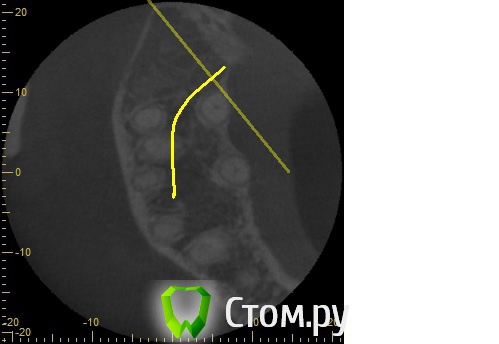

Анатолий М Опубликовано 21 апреля, 2014 Автор Поделиться Опубликовано 21 апреля, 2014 Снимок во время лечения делали? Коффердам и оптика использовались? На кт в тех срезах что Вы выложили кисты не вижу Снимки во время лечения делали три раза прицельные с иголками в каналах. Но они остались у врача. У меня их нет. Но она по ним кисты не видела. Коффердам использовали только при первом посещении когда вскрывали старую пломбу и прорабатывали каналы. При последующих посещениях при смене лекарст его не использовали так как кольцо на зубе плохо держалось и постоянно слетало. Плюс травмировало десну.Микроскоп использовали все три раза. По словам врача (врач высшей категории эндодонтист зав отделением):При вскрытии старой пломбы каналы практически не заполены цементирующим составом. Иструмент при вскрытии пломбы в каналы проваливался. Хотя стояла постоянна пломба. Из трех каналов лишь один был проработан до верхушки корня. Два других либо до половины либо на треть. Врачь полностью прошла все каналы и даже залезла за апекс. туда при первом пломбировании врач даже не пыталась лезть. При третьем посещении врач констатировала что каналы чистые. Никаких признаков инфекции нет. И белезненная перкуссия от чего то другого. Специально проводила ревизию каналов при втором и третьем посещении без анастезии что бы понять где болит. Но так и не поняла. Повела на консультацию к профессору в их стоматологи. Посмотрев контрольную КТ он сказал что там киста и надо удалять зуб! Похоже что мой врач с ним не очень согласна, хотя и спорить не стала поэтому отправила меня на консультацию к неврологу. Ниже срезы конрольного КТ после месяца лечения гидрооксидом кальция на воде. Срезы по дуге. Сделал как смог. Шаг срезов как я понимаю 1мм. Линия по перек дуги снимок номер 1 (см нумерацию в конце названия файла) Ссылка на комментарий